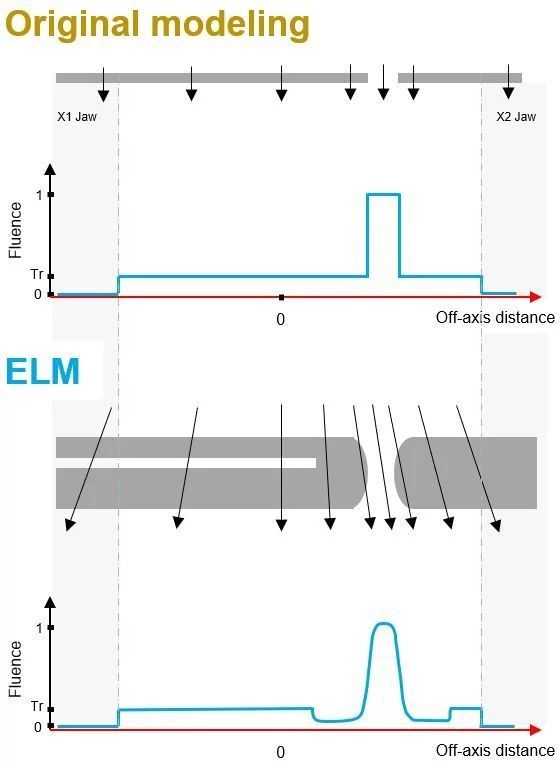

ELM is a step forward in more accurately modeling the MLC leaf tip end and drive screw and beam divergence. We’re seeing closer agreement between predicted and measured dose distributions, presumably due to improved MLC modeling.

We recreated many of the tests reported in the research paper by Ann Van Esch2 et al. Our testing showcased, among other positive observations, how much better ELM was in modeling the leaf tip and off-axis dose distributions, which are both critical in radiation therapy today with the increased use of small fields in SRS and SBRT.

I have rerun QA analyses on several plans with both our v15.6 and v18.0 algorithms and compared them to our measured results. Especially for smaller fields and those that are highly modulated, we are seeing improvements in IMRT QA pass rates. Even for the Static Wallpaper Test, a simple 16cm x 15cm field with static 4-cm openings, it was eye-opening to see the impact of ELM and the improvements in dose modeling on quality assurance measurements. Our gamma passing rates, using 2%/2mm for MapCheck 3 and EPID, improved from 92.7% and 89.5% to 97.3% and 97.2%, respectively.